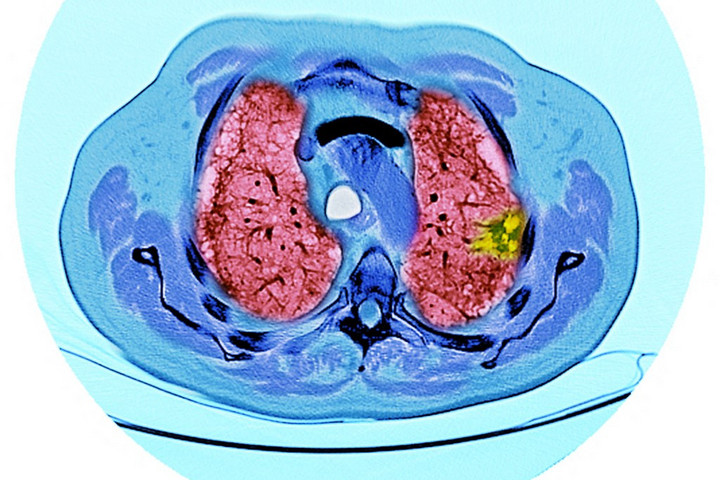

Igen, a dohányos tüdő állapota meglepően sokat javul a leszokás után, csak nem mindent és nem azonnal. A légutak „öntisztító futószalagja” újraindul, a légzésképesség javul, a tüdőrák-kockázata évről évre csökken. Ami viszont már elveszett a léghólyagok falából (emfizéma), az többnyire nem nő vissza. Nézzük végig alaposan, mit, mikor és miért javít a leszokás.

A dohányfüst ezt a rendszert bénítja meg, de a leszokás után hetek–hónapok alatt újraindul és egyre hatékonyabb. Ez a leszokás első nagy nyeresége. A másik mechanizmus az alveoláris makrofágok, a léghólyagok „falósejtjei” megeszik a mélyre jutó szennyeződéseket. Dohányzáskor tompábbak, leszokás után rendeződik a működésük, ami tovább segíti a takarítást.

És jön a sejtszintű meglepetés, egy nagy visszhangot kapott kutatás szerint ex-dohányosok légútjában újra elszaporodnak az alig mutált, „egészséges” hámsejtek, részben kiszorítva a füst által megsérült sejteket. Ez a kézzelfogható oka annak, hogy a rák-kockázat évek alatt látványosan csökken.

Évek múlva már mérhető tüdőfunkció-nyereségünk lesz. A történelmi jelentőségű Lung Health Study kimutatta, hogy a leszokók lényegesen lassabban veszítenek a kilégzési kapacitásból (FEV₁), mint akik folytatják. A különbség nagy része már az első évben jelentkezik és aki tartósan leszokik, az tartósan jobban is jár. 10–20 év múlva pedig zuhanó rák-kockázat mutatható ki.

10 év leszokás után a tüdőrák kockázata kb. a fele a tovább dohányzókénak; 15–20 évig tovább esik, több rákféleség kockázata is visszább megy. A soha nem dohányzók szintjét nem mindig éri el, de a különbség óriási.

Valami viszont nem fordítható vissza. Az emfizéma — amikor a léghólyagok falai elszakadoznak — strukturális károsodása. Gyógyszerekkel, légzőtornával, rehabilitációval lehet lassítani és a terhelhetőséget javítani, de a szövet nem épül vissza. Ezért kulcskérdés az időzítés, minél előbb tesszük le, annál többet mentünk meg.